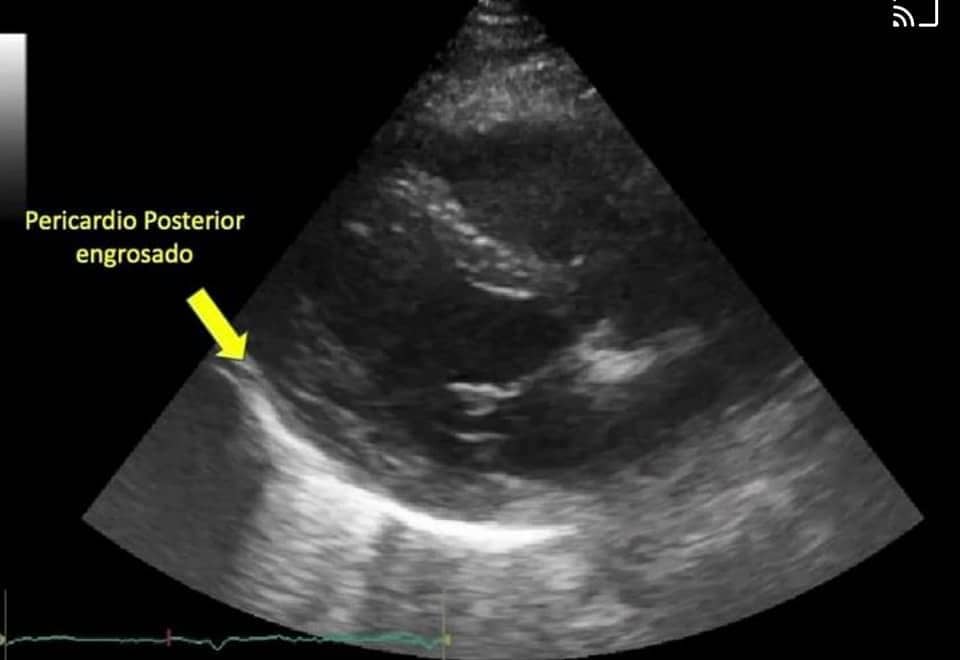

Hombre de 32 años, sin antecedentes crónicos ni cardiovasculares, 13 días previos con síndrome gripal, el día que acudió a valoración fue por dolor en el pecho opresivo-lancinante, muy intenso, irradiado a región esternal alta, aumentaba con la inspiración y movimientos rotatorios del tórax, reducía con el reposo,le presión arterial y frecuencia cardiaca normal, electrocardiograma compatible con pericarditis (inflamación de la bolsa que rodea al corazón), se da tratamiento mejorando a las 6 hrs sin complicaciones, se realiza ecocardiograma mostrando engrosamiento del pericardio. Seguimiento en la consulta sin molestias.